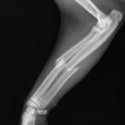

Wij komen regelmatig afwijkingen en ziekten van het steun- en bewegingsapparaat tegen. Ziekten aan het bewegingsapparaat worden vaak gekenmerkt door pijn; dieren komen niet overeind, bewegen minder of kunnen kreupel lopen. Soms is het noodzakelijk om röntgenfoto’s te maken om de oorzaak van de kreupelheid op te sporen. Hiervoor beschikken wij over een digitaal apparaat. Indien nodig kunnen röntgenfoto’s gemakkelijk met specialisten overlegd worden.

Vaak zal een bewegingsadvies gecombineerd met geschikte medicatie een oplossing bieden. In sommige gevallen zal een operatie noodzakelijk zijn om de klachten te verhelpen.